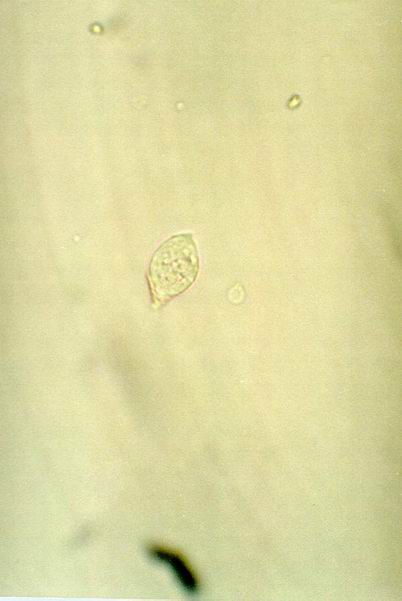

FOTOĞRAF 0143

Açıklama: 400x büyütmede idrar sedimenti mikroskopisi. Fotoğrafta 1 adet Trichomonas vaginalis görünüyor.